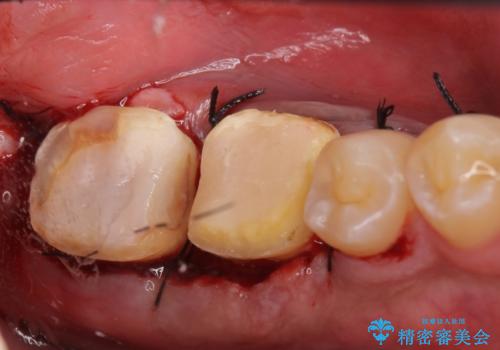

- 左下7の歯しみる、被せ物を被せてもすぐに外れてしまうといらっしゃった方の症例です。

左下に被せ物を被せるクリアランス(補綴のための上下のスペース)ないため、十分な歯冠長を確保するため歯冠長延長術を行いました。

その後歯肉の回復を待ち、フルジルコニアクラウンにて補綴を行いました。

歯冠長延長術とは歯肉弁根尖側移動術とも言い、歯の高さが低くクラウン(被せ物)による治療が難しい場合に、歯茎を歯根方向に下げることで歯の高さを確保する手術です。歯の高さが十分にあることで、外れにくいしっかりとしたクラウンを被せることができます。